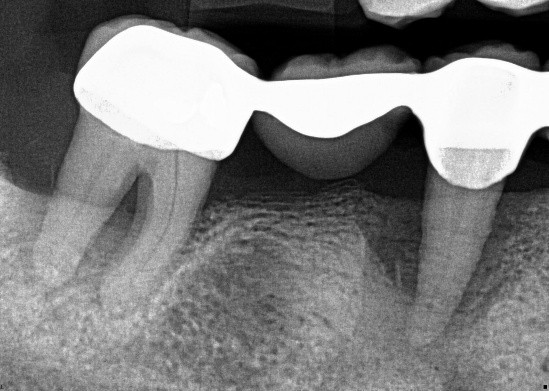

2. (Select ONE OR MORE correct answers)

The radiograph shows evidence of